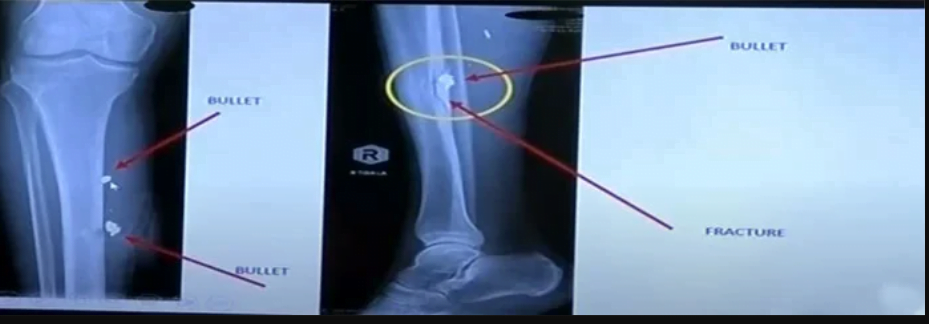

The details of Khan’s injuries, including a fracture among others, were underlined in Dr Sultan’s presentation of the X-ray scans for the party leader.

At the start of the press conference, Khan revealed that he had been shot four times and requested PTI stalwart, Dr. Faisal Sultan,Dr. Faisal Sultan to inform the public about his health.